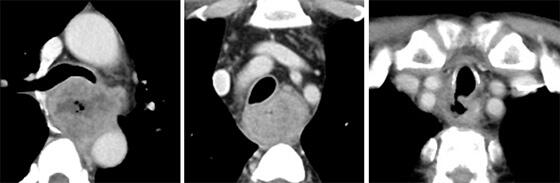

隣接臓器浸潤が疑われて切除困難・・?

多数の転移があって治癒は困難・・?

と思われる症例でも大丈夫です。他院で切除不能と診断されても実際切除可能な例は少なくありません。転移が多くても前治療で著効が得られれば十分治癒はあります。今は強力な補助療法があり、超進行がんであっても、そのresponse次第で結果は大きく変わります。

気管食道瘻が形成されているのですが・・・?

それでも大丈夫です。ご相談頂ければ準緊急で対応させて頂きます。我々はどんな症例でも可能性を目指して治療させて頂きますので、「困った・・?」と思われたらいつでもご連絡頂ければと思います。皆さんと協力して1人でも多くの食道がん患者を救うことができればと願う次第です。

腹臥位胸腔鏡下食道切除術で低侵襲に治療

当科では、白石治先生が積極的に低侵襲食道切除術に取り組み、高度進行がんでも胸腔鏡の拡大視と低侵襲性を最大限に活用して切除しており、ほぼ全例が鏡視下による低侵襲手技で手術が完結しています。特に左側に高度進行した食道がん症例に対しては、白石先生が考案して積極的に応用している左右の胸腔から胸腔鏡下に剥離を行い、安全かつ良好な視野の下で手術を行うことで治癒切除率の向上を図っています。